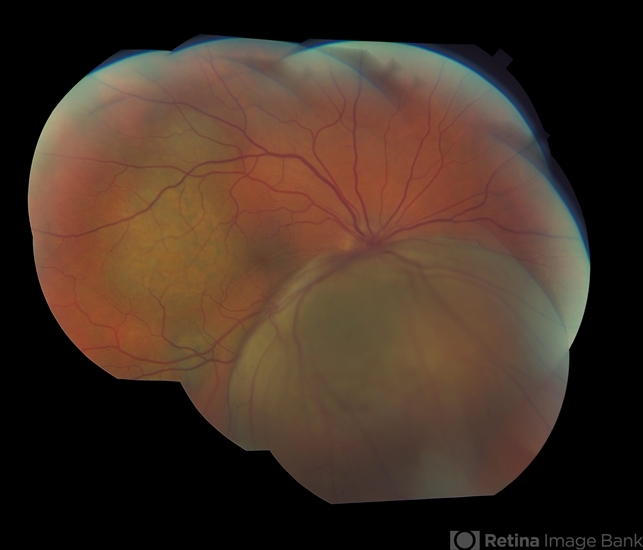

This is an excellent montage of this inferior malignant melanoma showing marked elevation and detachment in this patients right eye. You have done our profession a great service Kathy, as well as performed expert documentation for the patient, and, for your physician.

- Metastatic malignant melanoma in 44-year-old man.